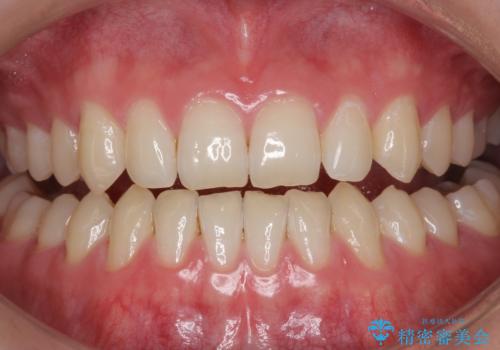

- 元の色は普通より少し黄色めの白さでした。お口の中は、プラーク等付着してなくてきれいな状態でした。

ホワイトニングエクセレントコースで3回照射の施術をしました。